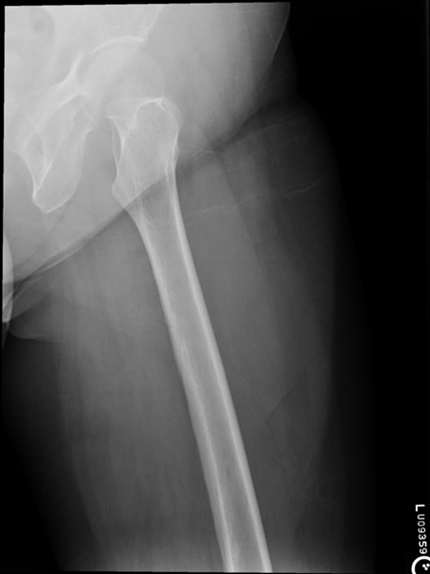

AP Femur

•Evidence of proper collimation and the presence of a side marker placed clear of the anatomy of interest

•Most of the femur and the joint nearest to the pathologic condition or site of injury (a second projection of the other joint is recommended)

•Femoral neck not foreshortened on the proximal femur

•Lesser trochanter not seen beyond the medial border of the femur or only a very small portion seen on the proximal femur

•No knee rotation on the distal femur

•Gonad shielding when indicated, but without the shield not covering proximal femur

•Any orthopedic appliance in its entirety

•Bony trabecular detail and surrounding soft tissues

Lesser trochanter is on, leg is not rotated in, under-rotated, hanging out too laterally

Leg was not internally rotated

No repeat, lesser trochanter can hardly see

Missing anatomy

slight medial rotation